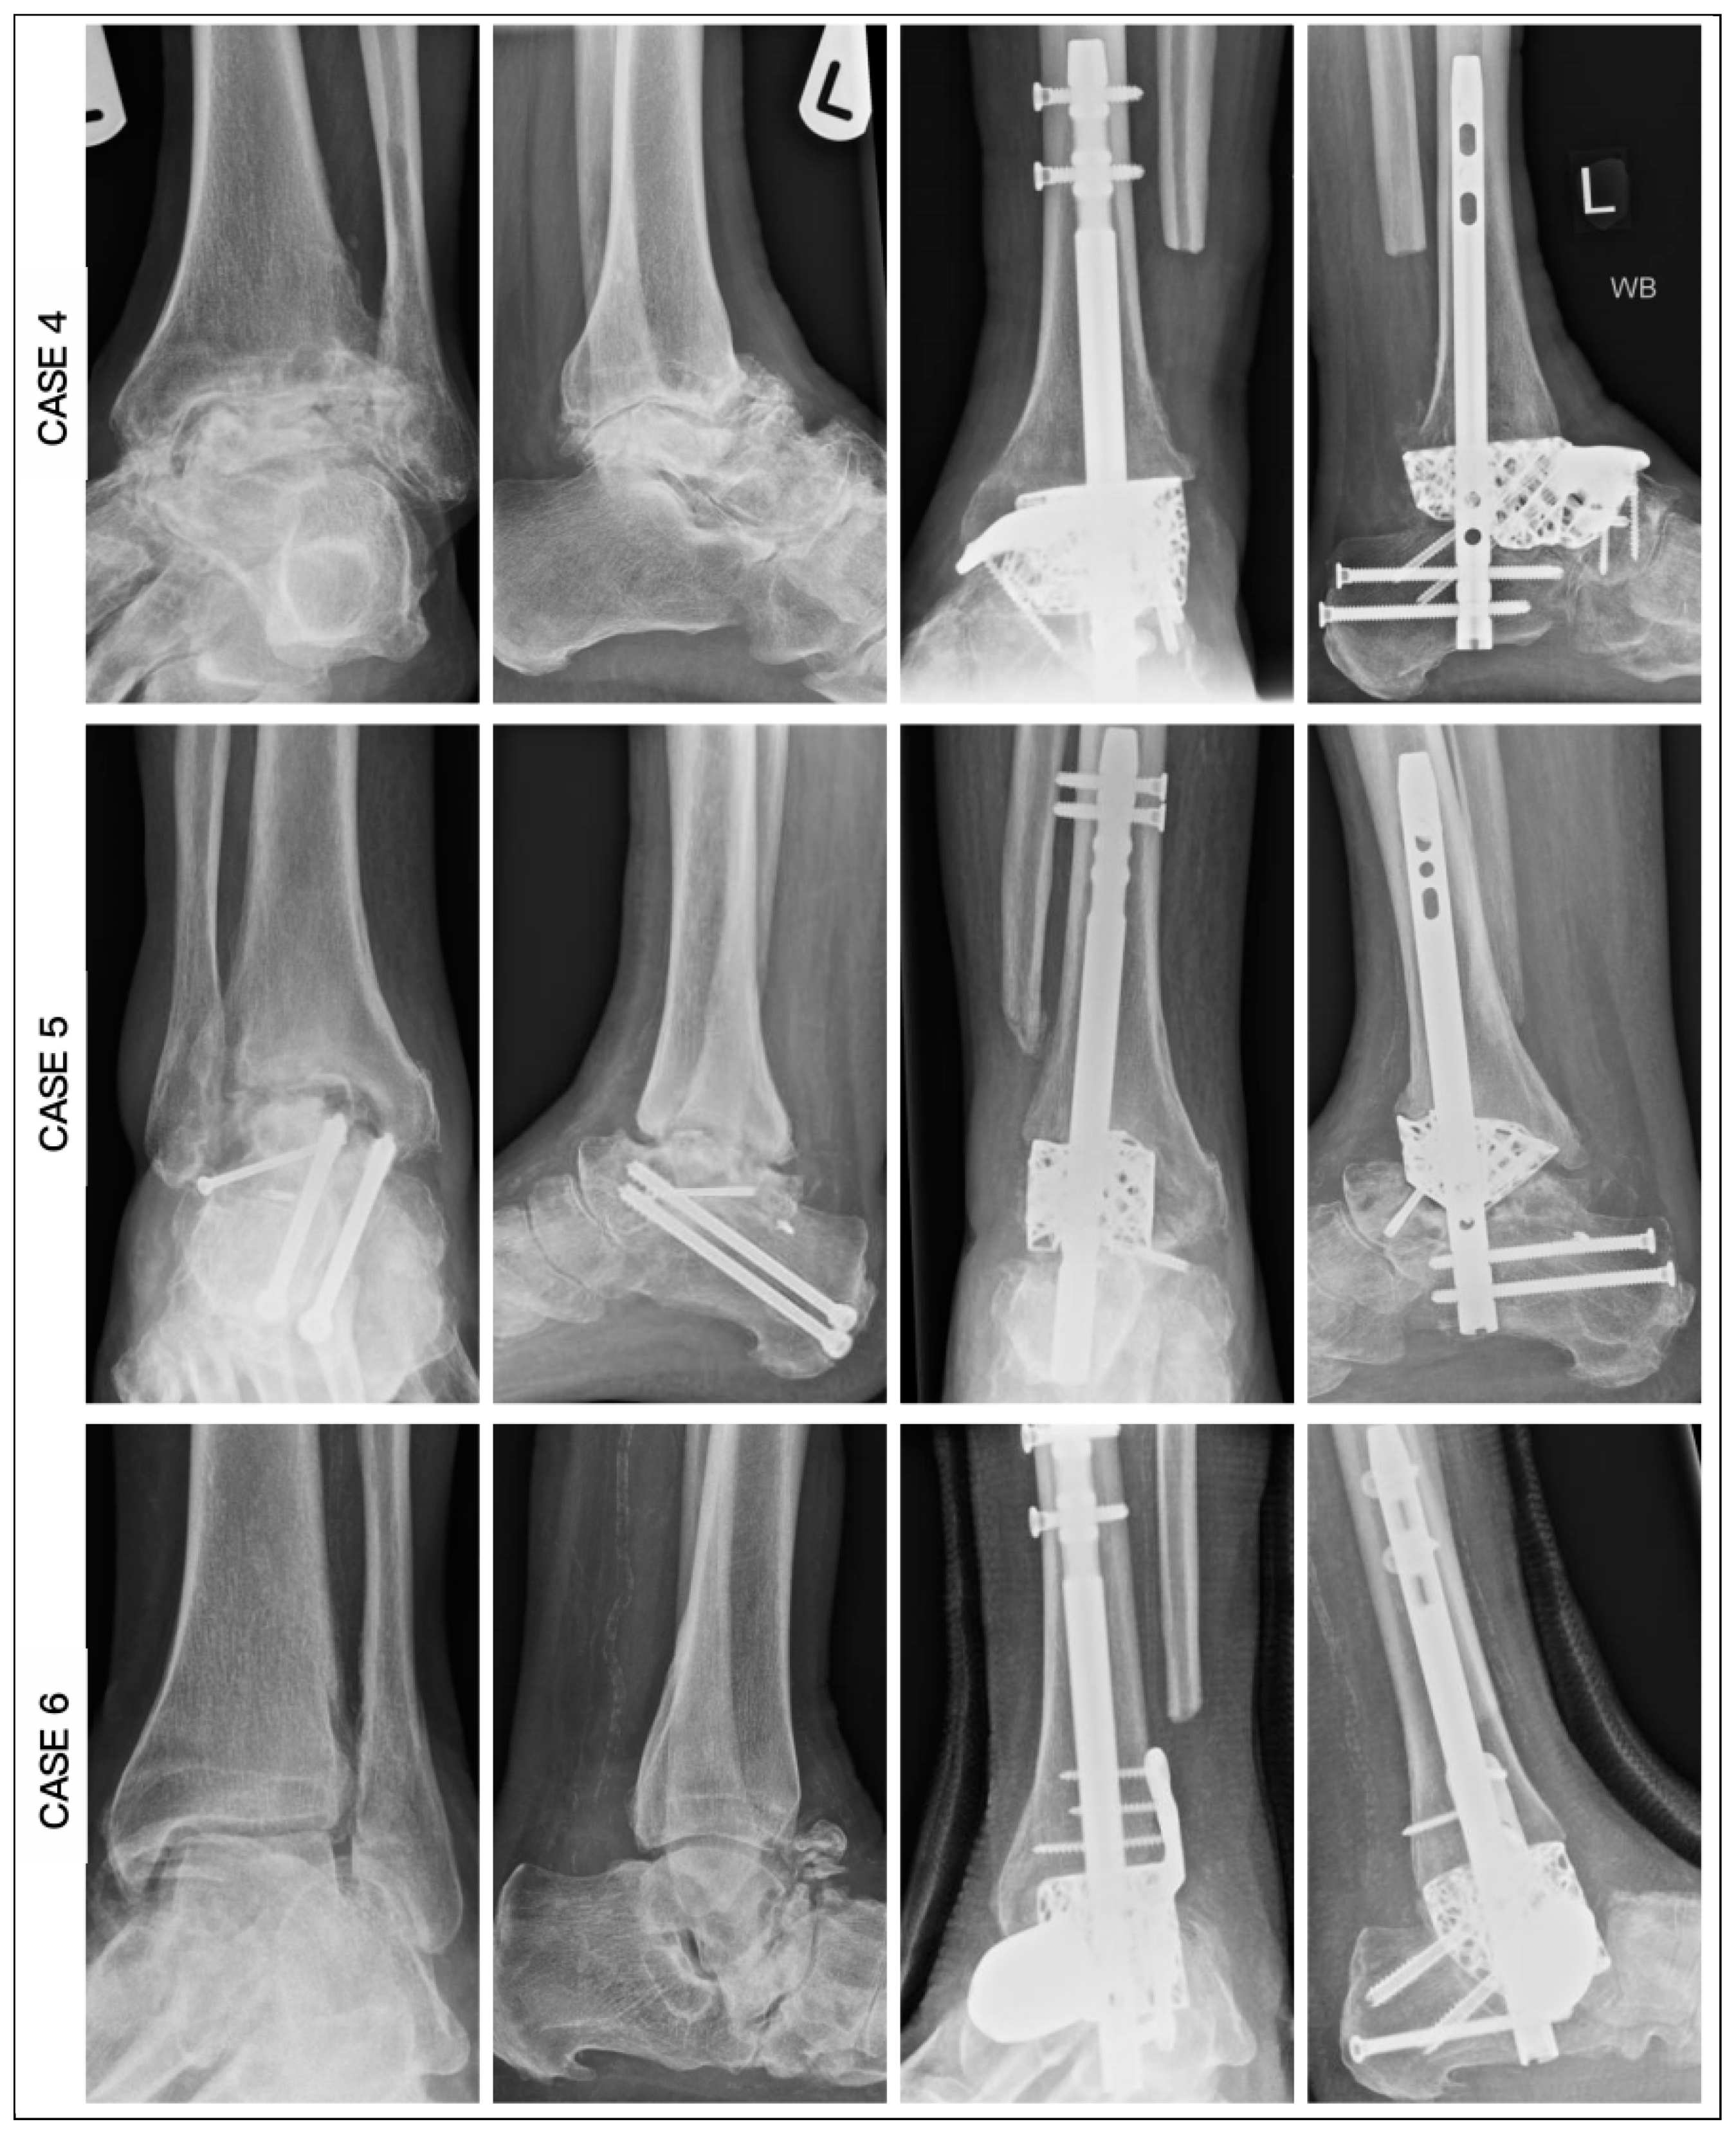

3. Results

| CASE | 1 | 2 | 3 | 4 | 5 | 6 |

|---|---|---|---|---|---|---|

| Age | 62 | 59 | 60 | 60 | 78 | 67 |

| Diagnosis | OM | OM | OM | AVN | AVN | AVN |

| Smoking | No | Yes | Yes | No | Yes | No |

| BMI | 26.5 | 27.4 | 27.4 | 28.2 | 32.1 | 35.4 |

| Medical | Nil | IHD, CKD, PAD | CKD | CKD, PAD | DM | IHD, DM, CKD, CN |

| HbA1c | 36 | 39 | 39 | 41 | 49 | 70 |

| CRP | 8 | 7 | 16 | 9 | 10 | 6 |

| Hb (g/L) | 113 | 105 | 132 | 146 | 113 | 114 |

| Past surgery | 5 | 3 | 3 | 0 | 1 | 0 |

| Modification | Tibial and Navicular Flange, Nail | Navicular Flange, Nail | Tibial and Navicular Flange | Navicular Flange, Nail | Nail | Articulating Navicular Extension, Tibial Flange, Nail |

| Duration of surgery (min) | 255 | 220 | 162 | 210 | 190 | 205 |

| Wound Healing (days) | 42 | 40 | 20 | 29 | 32 | 45 |

| Union (weeks) | 25 | 19 | 16 | 14 | 27 | 20 |

| Ambulation (weeks) | 28 | 21 | 18 | 16 | 29 | 22 |